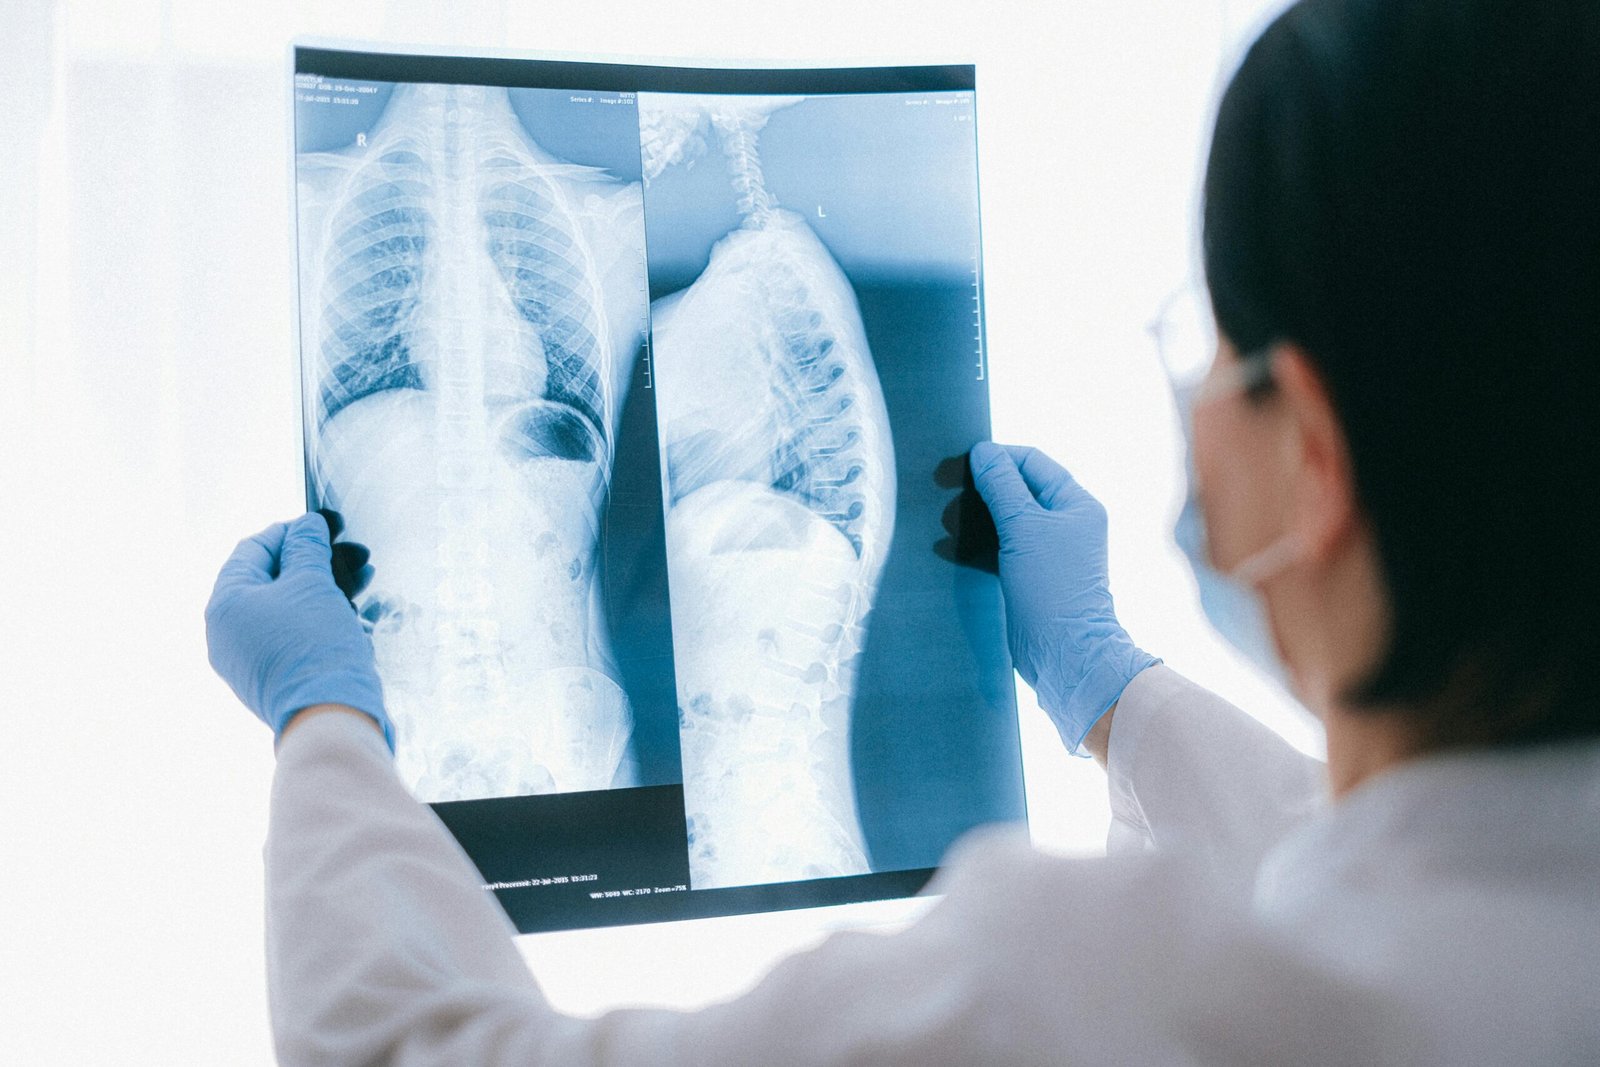

How Is a Slipped Disc Diagnosed?

Accurate diagnosis is essential to avoid unnecessary procedures.

- Detailed clinical evaluation

- Neurological examination

- MRI scan (gold standard)

- Correlation of imaging with symptoms (pain-generator approach)